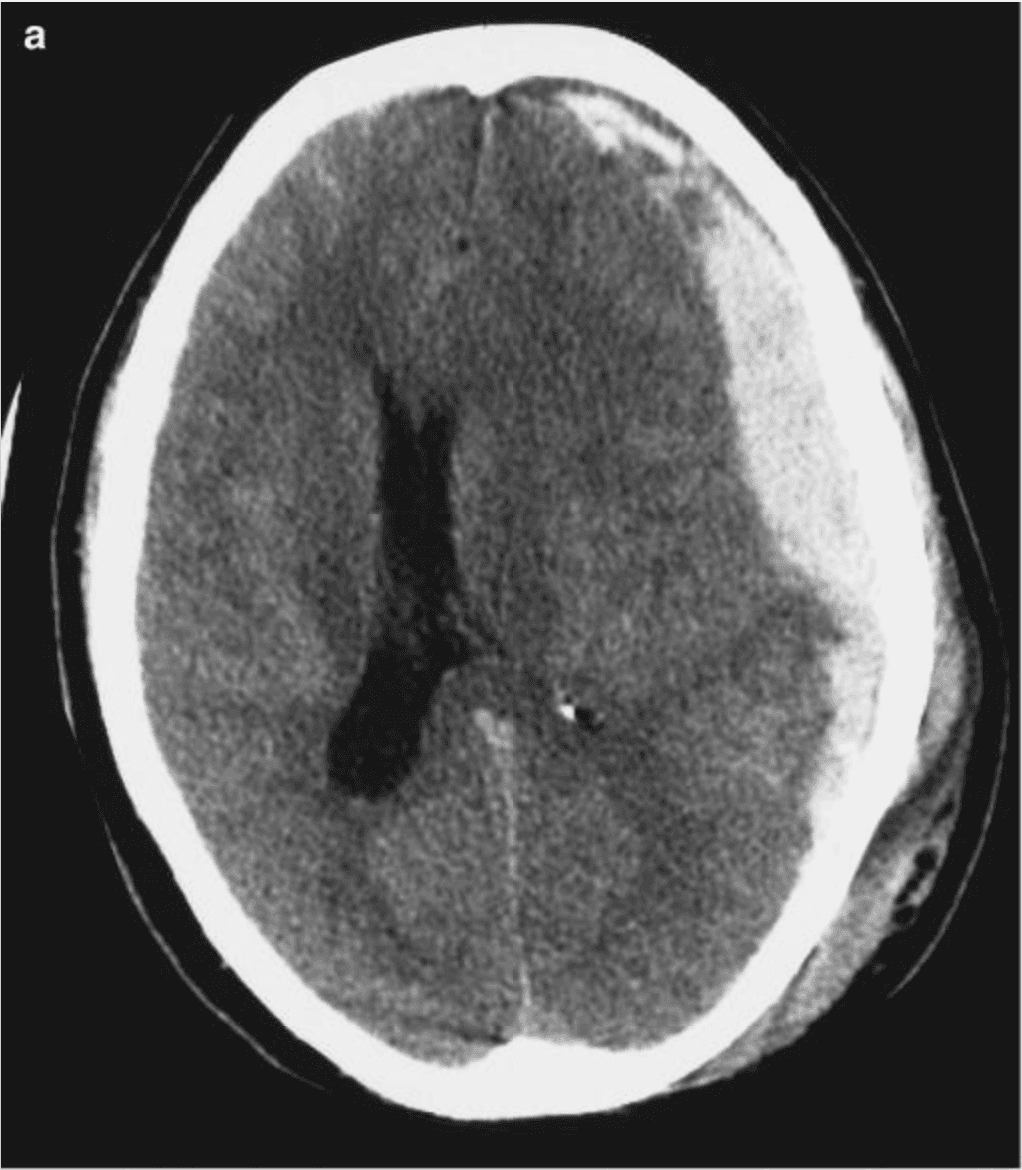

The clinical power of this arc is anatomic. It runs through the dorsal midbrain and along the tentorial edge where CN III is vulnerable to compression. A new anisocoria, a sluggish response, or a unilateral fixed dilated pupil points straight to this anatomy — uncal herniation, PCom aneurysm, or ipsilateral mass effect — often before other localizing signs appear.

The anisocoria story matters most. A new, persistent asymmetry of ≥ 0.5–1 mm is often the first localizing sign of uncal herniation, evolving mass effect, or CN III compromise — and it is precisely the signal most prone to being missed on a subjective exam. Martins et al., in 748 severe-TBI patients, reported an adjusted OR of 11.52 for death with bilateral mydriasis and 2.65 with anisocoria versus isocoric pupils DOI (PMID 19590314). Tien et al. found that 100% of GCS-3 trauma patients with bilateral fixed dilated pupils died, versus 42% mortality in those whose pupils remained reactive DOI (PMID 16508482). Brennan, Murray and Teasdale formalised this in the GCS-Pupils score: mortality rises from 51% at GCS 3 to 74% at GCS-P 1 DOI (PMID 29631516). The 2024 NINDS TBI Classification Initiative now recommends that “pupillary reactivity should be documented in all patients” with TBI, recorded separately from the GCS DOI (PMID 40393504).